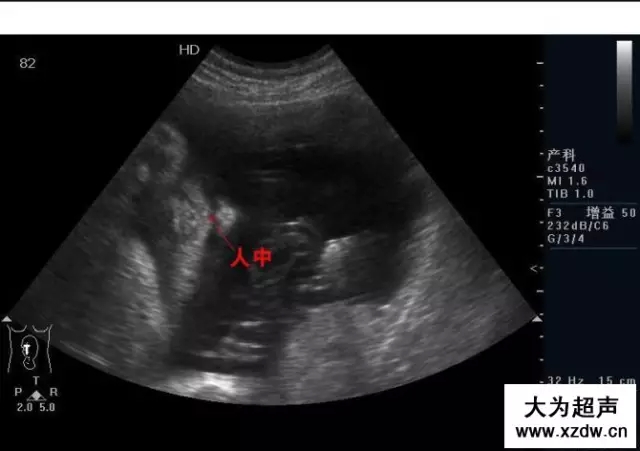

產(chǎn)科超聲正常圖片